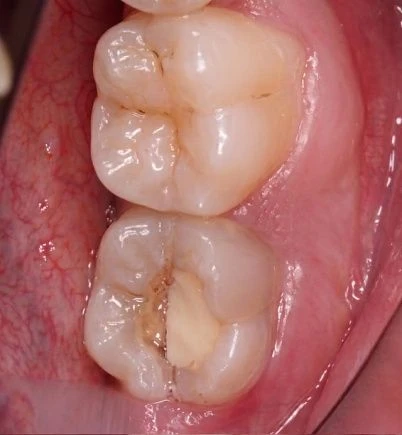

Наши работы

В стоматологической клинике «Доктор Смайл» в Москве проводится микропротезирование зубов. Наша клиника оснащена современным профессиональным оборудованием и имеет собственную зуботехническую лабораторию, а специалисты имеют достаточный опыт проведения подобных процедур.

Стоматологи-ортопеды в своей работе применяют инновационные технологии, целью которых является не только создание красивой улыбки, но и восстановление утраченных функций. Мы следим за качеством микропротезирования в стоматологии «Доктор Смайл», которое соответствует международным стандартам.